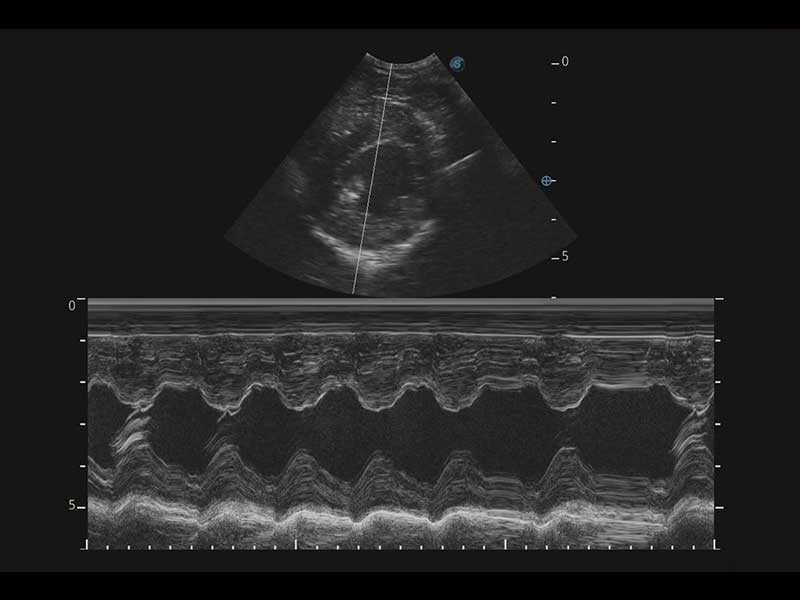

Az X Series Vet platform egy laptop kialakítású színes Doppler ultrahangrendszer, amely kiemelkedő képalkotó technológiáival van felszerelve, és professzionális állatorvosi szoftvereket kínál a kis kedvtelésből tartott állatoktól a nagy haszonállatokig. Kristálytiszta képalkotása és gördülékeny munkafolyamata új, továbbfejlesztett vizsgálati élményt biztosít, amely a magabiztos diagnózishoz szükséges pontosságot nyújtja.

Mivel az X Series Vet a SonoScape legújabb képalkotó technológiáit alkalmazza a nagy felbontású és mély penetrációjú képek előállításához, nagy mennyiségű diagnosztikai információ jeleníthető meg az ultrahang képernyőn. A továbbfejlesztett képminőség gyorsabb és pontosabb vizsgálatokat tesz lehetővé bármely állatfaj esetén.

A hatékonyságot, egyszerűséget és sokoldalúságot ötvözve az X Series Vet kiváló választás lógyógyászati vizsgálatokhoz. Speciális transzducerekkel és ló specifikus szoftverekkel felszerelve könnyedén készít lenyűgöző képeket az olyan alapvető alkalmazási területeken, mint az MSK, a reproduktív szervek vizsgálata, valamint a megfelelő penetrációt biztosítja hasi és kardiológiai vizsgálatokhoz is.